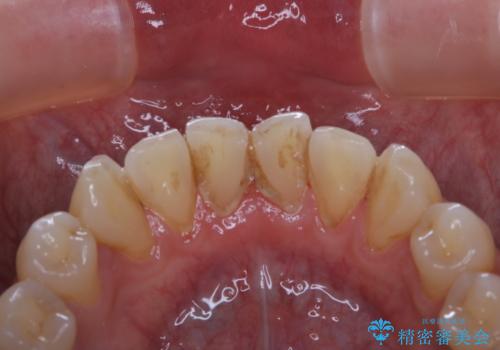

- 40年ほど歯科医院へ行ってなく、ザラつきがきになるとの事で来院されました。最近は普段の歯磨きの際、出血することがあり、歯ブラシ指導も希望されました。

お口全体に、歯垢・歯石が付着していたため、自費クリーニング(PMTC)60分コースを行い、徹底的に除去しました。

40年ぶりの来院との事で全体的に、古くからの歯垢・歯石が硬く多く付着していたため、自費クリーニング(PMTC)60分1万円+TAXコースを行いました。

日々の磨き残しなどをそのまま放置すると、細菌が固まり硬い歯石になります。

歯石になってしまうと、とても硬く、歯ブラシで取り除くことが出来なくなります。